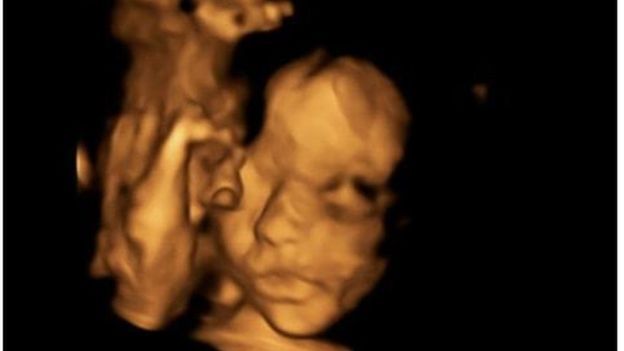

أجرى أطباء بريطانيون عملية في العمود الفقري لجنين بينما كان لا يزال في رحم أمه.

وقد فتح الرحم خلال العملية التي استمرت 4 ساعات، وتمكن الأطباء من إجراء رتق في الجزء الخلفي من العمود الفقري.

وفتح الرحم خلال العملية الجراحية التي أجريت في الأسبوع الرابع والعشرين من الحمل ورفع الجنين في وضع يسمح بالوصول إلى عموده الفقري وإجراء الجراحة ومن ثم إعادة الحبل الشوكي إلى مكانه.